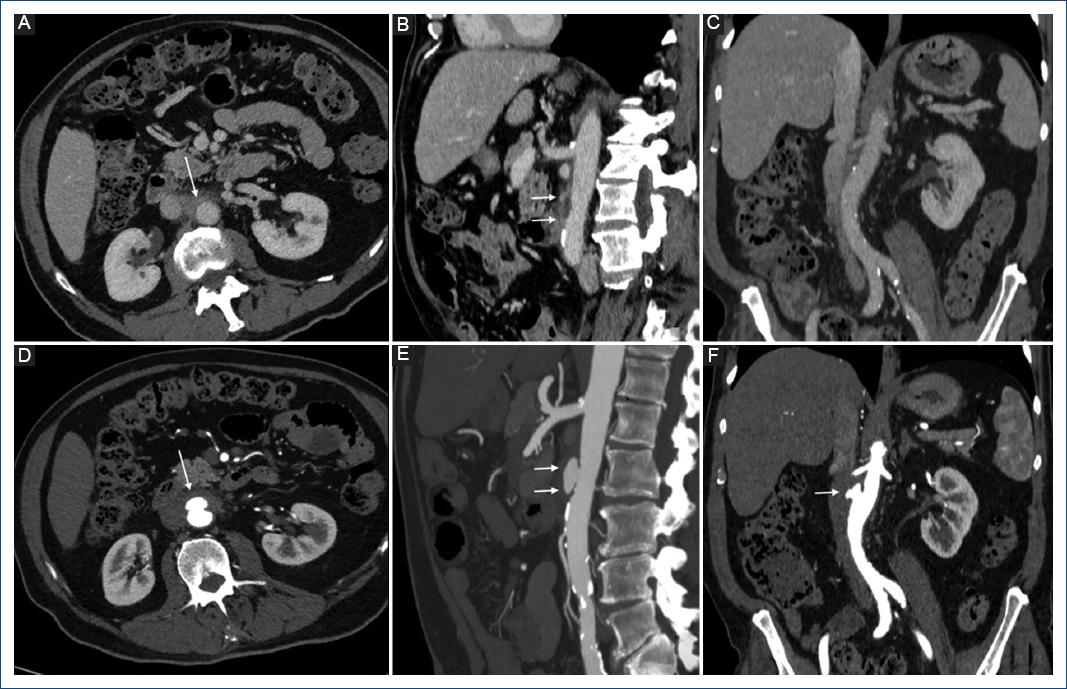

Paciente de sexo masculino de 78 años de edad, con antecedente de hipertensión arterial sistémica (HAS) y diabetes mellitus tipo 2 (DM2) descompensada, quien consultó por fiebre, mialgias, artralgias y estado confusional agudo. A su ingreso a sala de urgencias se le realizó una tomografía computarizada (TC) cerebral, la cual resultó normal; posteriormente, se le realizó una punción lumbar, cuyos análisis bacteriológicos fueron negativos. Ante la ausencia de foco infeccioso detectable se decidió dar egreso, pero el paciente regresó al día siguiente con un nuevo pico febril. En esta ocasión, se tomó urocultivo y hemocultivo, resultando este último positivo para Salmonella, por lo cual se dio tratamiento antibiótico con ciprofloxacino. Veinte días después, el paciente consultó nuevamente por dolor en el flanco derecho y persistencia de fiebre pese al tratamiento, por lo cual se decidió realizar una tomografía abdominal, detectándose cambios inflamatorios de algunas asas de íleon y la presencia de estriación grasa periaórtica a nivel infrarrenal (Fig. 1). Se recomendó al paciente realizarse un estudio de seguimiento; sin embargo, este decidió realizar un viaje al extranjero, donde presentó un nuevo episodio de fiebre y desorientación, por lo cual se realizó durante su viaje una resonancia magnética (RM) y un electroencefalograma (EEG), los cuales el paciente refiere que resultaron normales. Dos meses después de su primera consulta, acudió a realizarse estudios de control, donde se detectó elevación de la proteína C reactiva (PCR) y la formación de un aneurisma sacular en la aorta abdominal infrarrenal, de 3.5 cm de diámetro máximo, con persistencia de los cambios inflamatorios periaórticos (Fig. 1). Con estos hallazgos, se decidió la hospitalización del paciente por alta sospecha de aneurisma infeccioso, por lo cual se realizó planificación quirúrgica. El paciente fue ingresado a sala de operaciones, donde se realizó cirugía abierta mediante laparotomía, encontrándose cambios inflamatorios periaórticos y un aneurisma sacular en el segmento infrarrenal de la aorta abdominal, sin rotura. Se realizó desbridamiento y resección de 4 cm de la aorta abdominal, incluyendo el aneurisma, y se colocó injerto de dacrón impregnado con rifampicina, junto con un parche de epiplón. La cirugía finalizó sin complicaciones; sin embargo, el paciente fue ingresado de manera preventiva a la unidad de cuidados intensivos, para monitorización estricta. Las muestras del tejido aórtico enviadas a microbiología resultaron positivas para Salmonella resistente a quinolonas. El paciente evolucionó satisfactoriamente, dándose de alta 10 días después de la cirugía. Su tomografía de control realizada tres meses después del procedimiento mostró permeabilidad del injerto, con reducción de los cambios inflamatorios periaórticos y ausencia de nuevos aneurismas (Fig. 2). Actualmente, el paciente se encuentra asintomático respecto a la patología abdominal de base y sin hallazgos laboratoriales de proceso inflamatorio o infeccioso. Sin embargo, se documentaron datos de nefropatía crónica y persistencia de hiperglucemia, por lo cual se espera seguimiento mediante endocrinología.

Figura 1 Tomografía multicorte inicial (A, B y C) y de seguimiento (D, E y F), con cortes a nivel similar entre ambos estudios para comparación. A: corte axial en fase venosa que muestra estriación grasa y densidad de partes blandas a nivel periaórtico, hallazgo correspondiente con proceso inflamatorio agudo (flecha). B: reconstrucción sagital que muestra la extensión de los cambios inflamatorios periaórticos (doble flecha) inferior al origen de la arteria mesentérica superior. C: reconstrucción coronal que demuestra ausencia de dilataciones aórticas patológicas. D: corte axial en fase arterial de la tomografía de seguimiento, donde se observa aumento de la densidad de partes blandas periaórtica, con formación de una lesión sacular en la pared anterior de la aorta, la cual muestra realce similar al vaso. E: reconstrucción curva multiplanar en proyección de máxima intensidad que confirma la formación de un aneurisma sacular (doble flecha) en el sitio donde se observaron cambios inflamatorios en B. F: la reconstrucción coronal muestra que el aneurisma (flecha) se encuentra inferior al origen de ambas arterias renales, las cuales están respetadas.

El estudio de imágenes ideal para pacientes con aneurismas infecciosos es la TC; la RM es una alternativa aceptable en pacientes alérgicos al contraste yodado1,4. El ultrasonido puede ser útil en la detección de los aneurismas aórticos abdominales, pero su capacidad para detección de hallazgos inflamatorios es limitada1. Los hallazgos de aortitis preceden a la formación del aneurisma y consisten en irregularidad de la pared arterial asociado a edema y/o masa de partes blandas periaórtica, la cual puede formar zonas necróticas de baja densidad1,4,9. En nuestro paciente, el único hallazgo presente previo a la formación del aneurisma fue la estriación de la grasa periaórtica. El gas periaórtico es infrecuente y no estuvo presente en nuestro caso1,9; sin embargo, ha sido reportado en hasta el 92% de los casos de aneurisma micótico secundario a Clostridium septicum11. El aneurisma infeccioso aparece como una dilatación focal sacular, con realce tras administrar contraste1. La luz puede ser central o excéntrica y puede ser multiloculada1. La calcificación de la pared del aneurisma y la trombosis son hallazgos raros1.